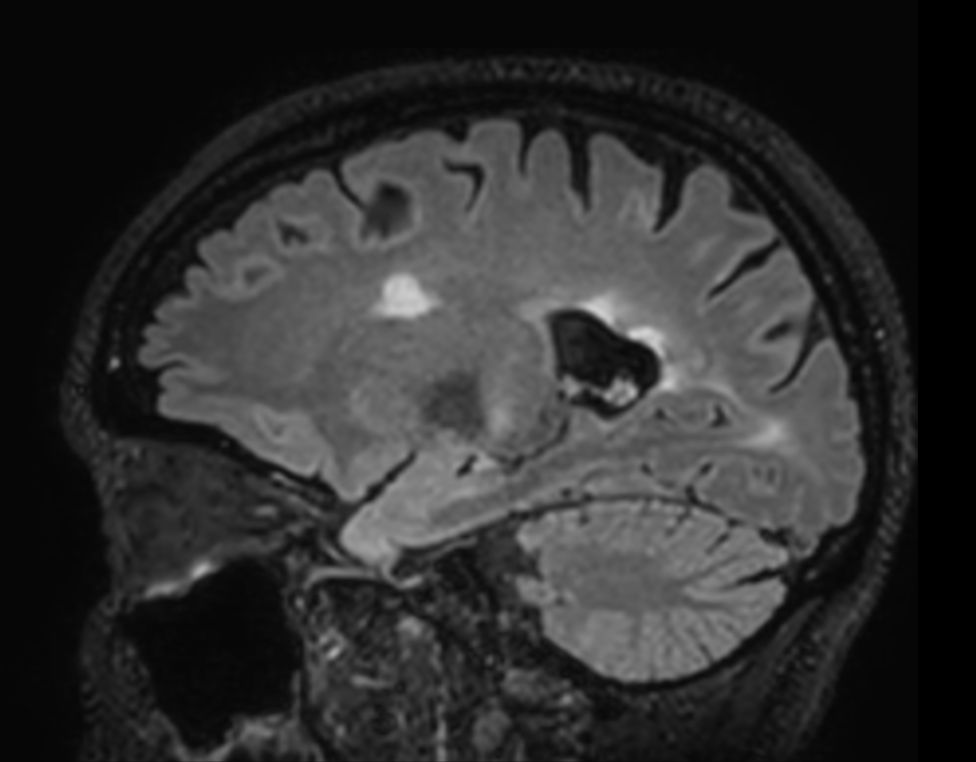

3D T2w FLAIR BrainVIEW Compressed SENSE

3D T2w FLAIR BrainVIEW (reformat) Compressed SENSE